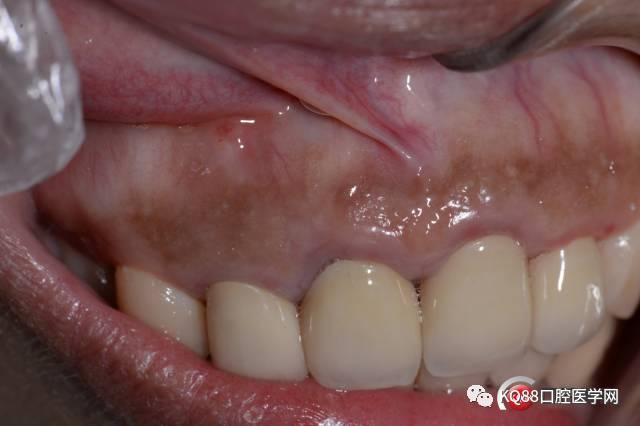

可以清楚的看见根尖唇侧骨板的破坏和根尖囊肿,好了刮除囊肿

可见牙胶尖,然后开始用球转去除周围一些感染的牙槽骨,同时根尖备洞准备倒充填,这个病例因为根尖只是远中有骨质破坏,根尖的近中是完整的,所以没有截根